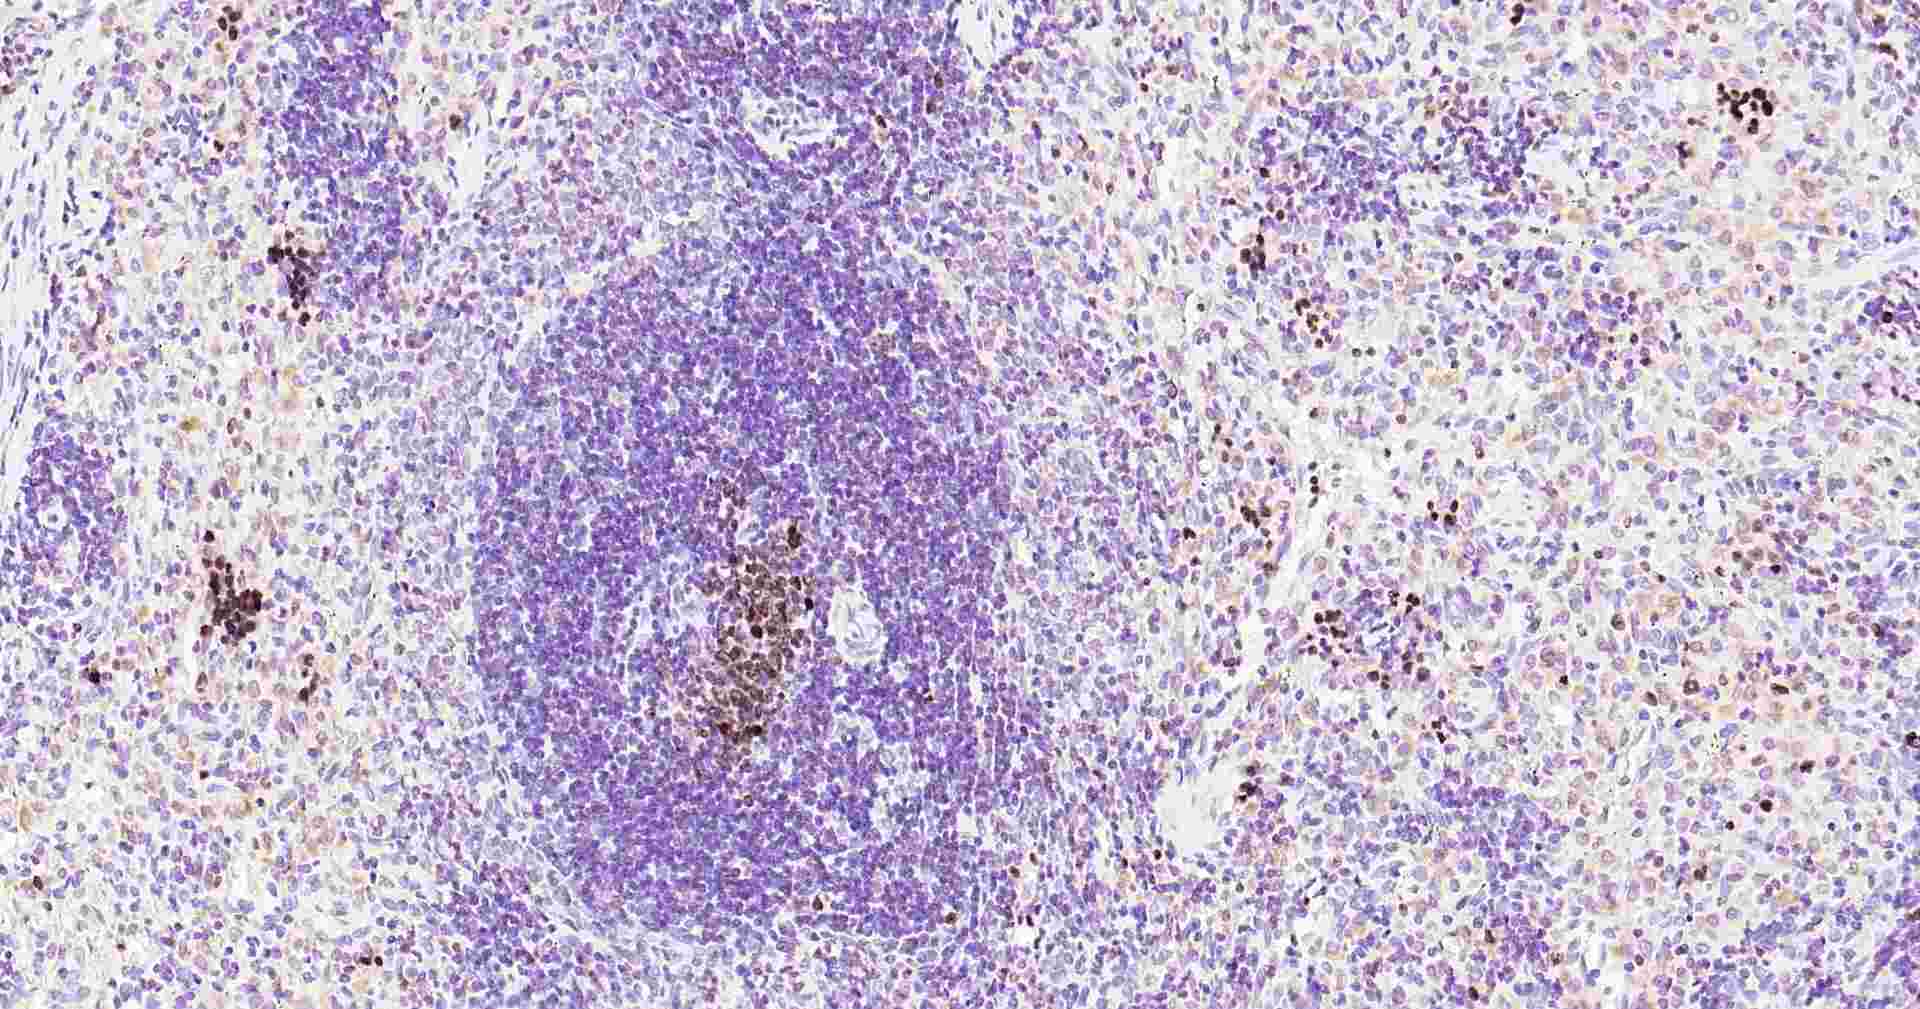

Immunohistochemical analysis of paraffin embedded rat spleen tissue slide using IHC0246R (Rat ki-67 IHC Kit).